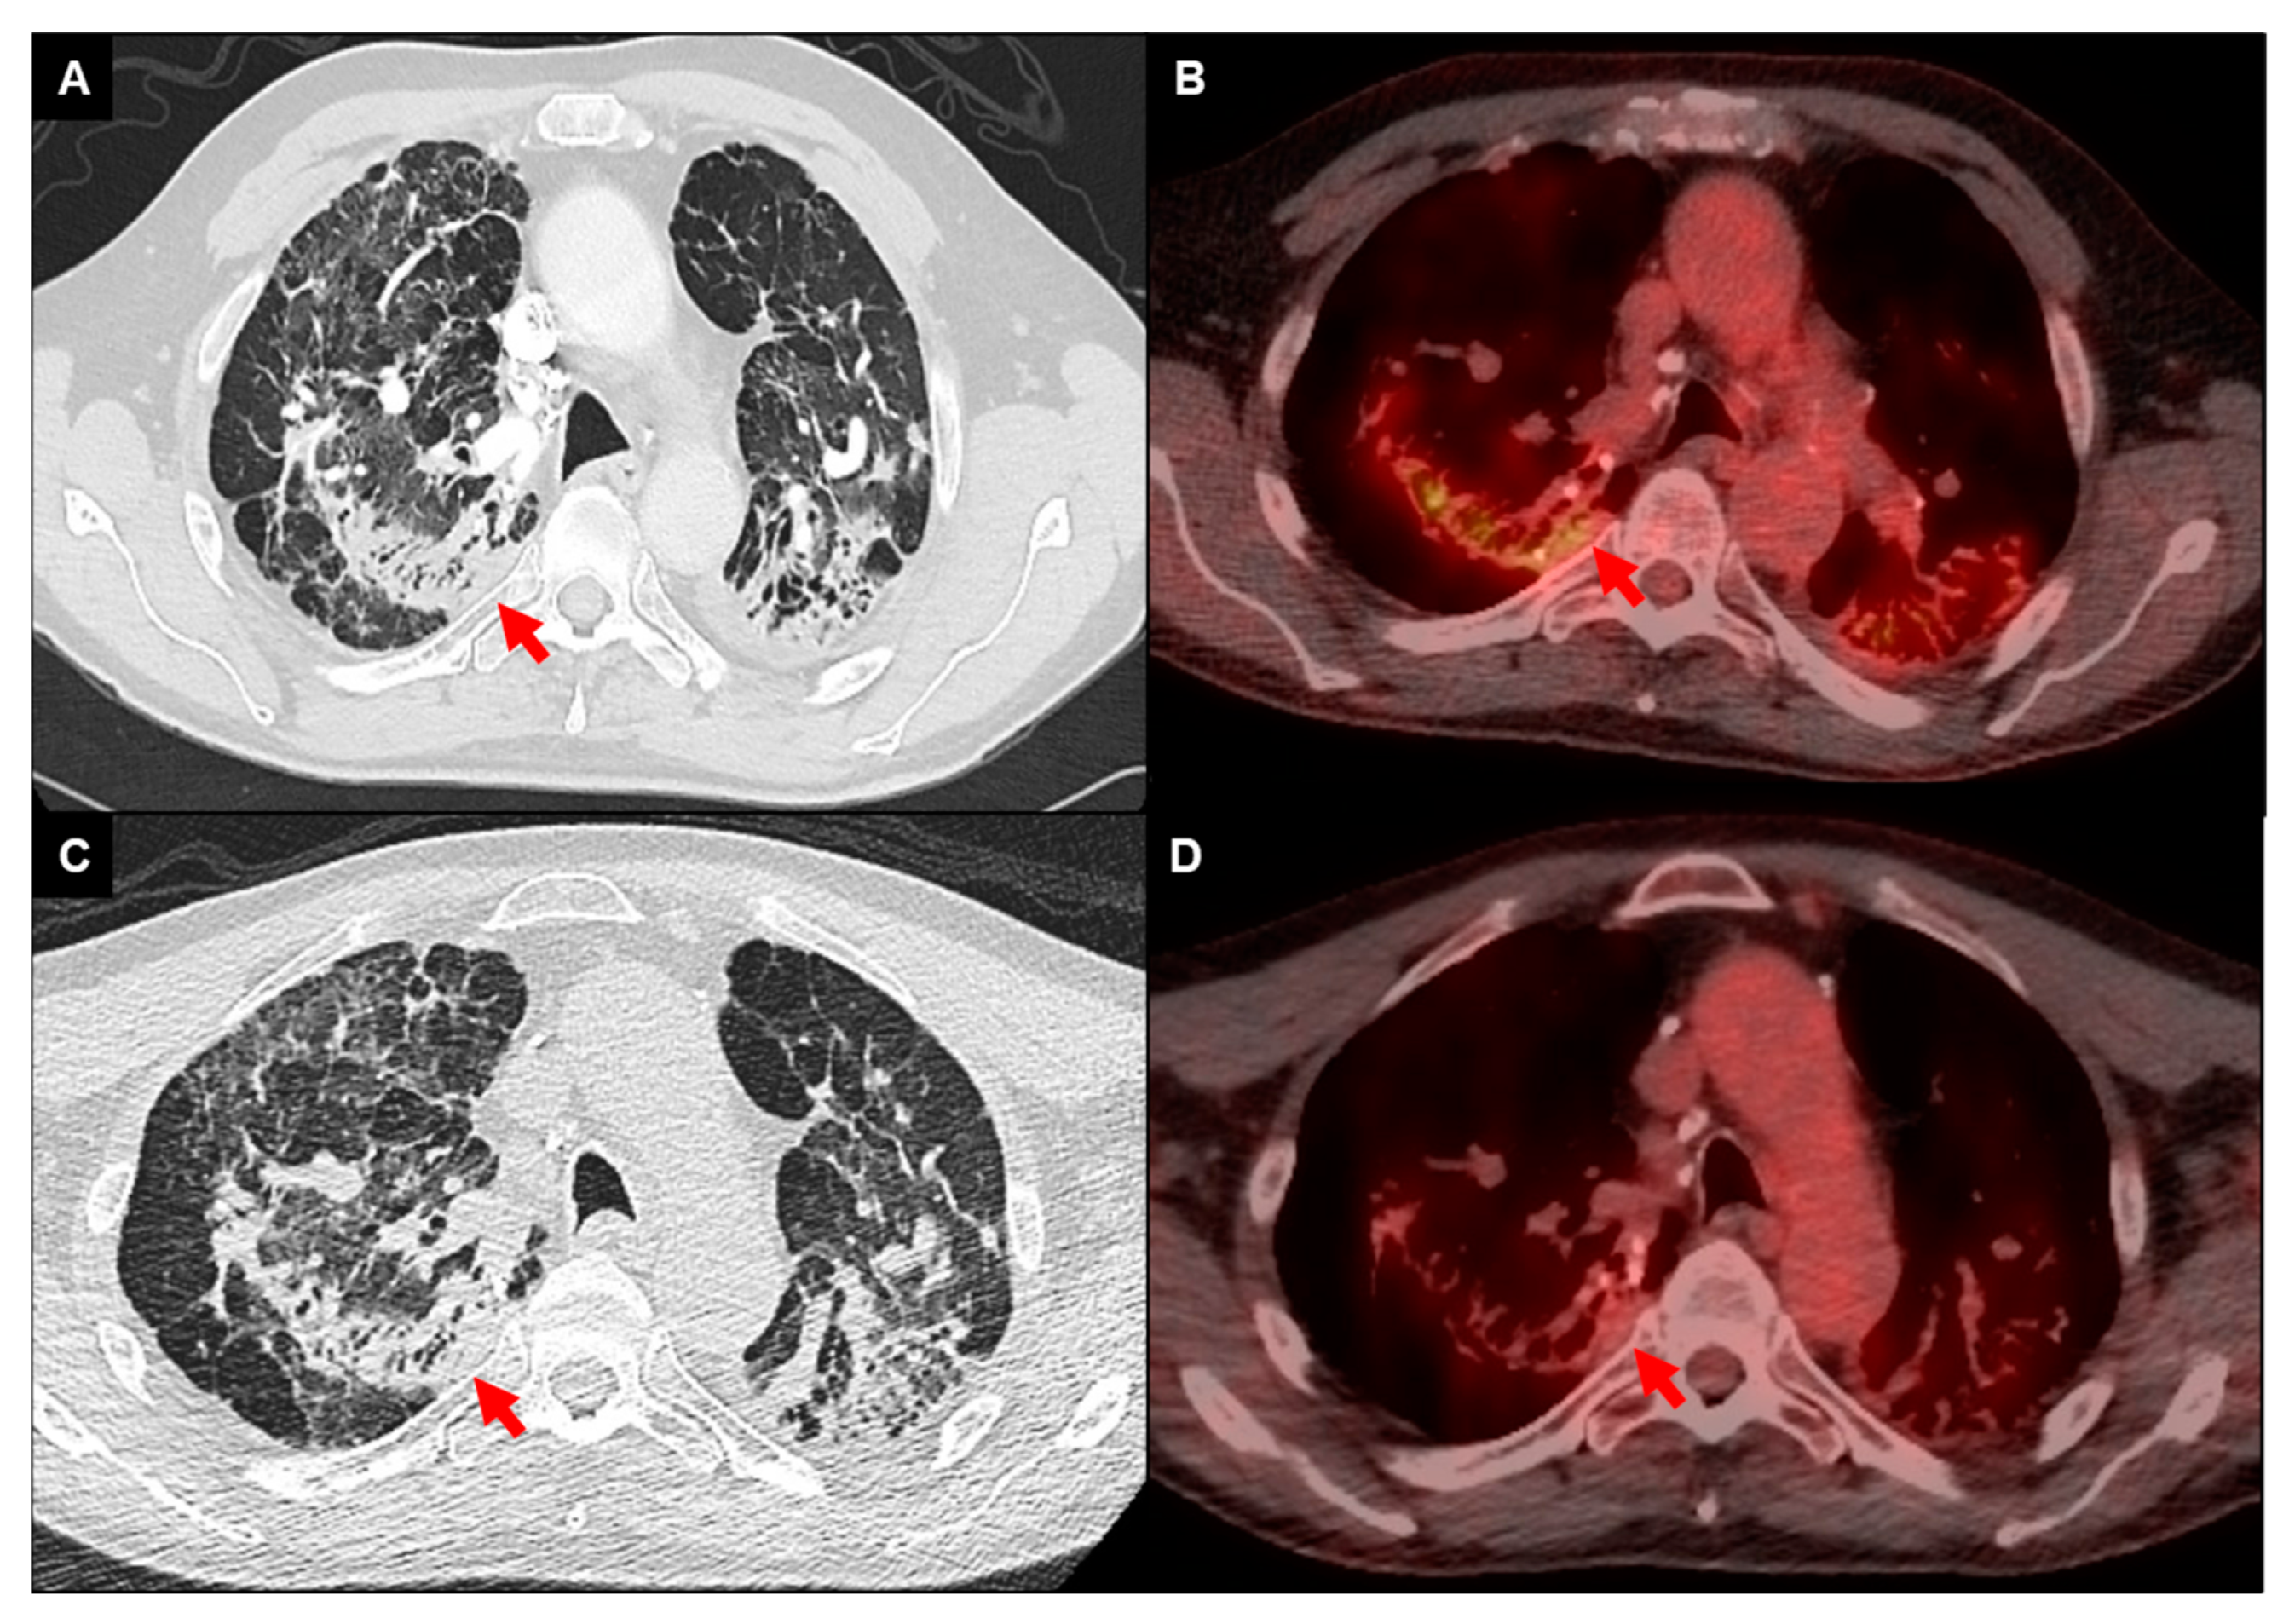

Fluorodeoxyglucose positron emission tomography integrated with computed tomography (FDG-PET/CT) in combination with cardiac MRI is predominantly used for the diagnosis and management of cardiac sarcoidosis [3,59]. In pulmonary sarcoidosis, FDG-PET/CT has exhibited a high sensitivity rate ranging between 94% and 100% in identification of ongoing inflammatory processes (Figure 3) [60,61]. Few studies have investigated its diagnostic use in pulmonary sarcoidosis [62,63,64]. One retrospective study involving 95 patients, with 85% demonstrating signs of fibrotic disease, found that the severity of pulmonary involvement as assessed by HRCT and lung function parameters was associated with increased FDG uptake at a threshold standardized uptake value (SUVmax) of greater than or equal to 2.5 [63]. Another study assessed the role of FDG-PET/CT in comparison with HRCT to identify sarcoidosis activity, and found a discordance rate of greater than 50% between FDG uptake and pathologic changes on HRCT. The presence of active nodal disease, active parenchymal changes, and disease recurrence in extrapulmonary regions were additional findings noted on FDG-PET/CT not discernible on HRCT [64].

Figure 3.

FDG-PET/CT imaging of a 68-year-old male with fibrotic pulmonary sarcoidosis on chronic methotrexate with metabolically active infiltrates (arrows) in the right upper lobe and left upper lobe extending into the pleura (A,B); reduced density and activity on follow-up imaging 12 months after the addition of anti-TNF-alpha inhibitor (C,D).

In the context of disease activity monitoring, a limited number of studies found that patients who exhibited reductions in SUVmax values following glucocorticoid therapy experienced lower rates of relapse, in contrast to individuals without reduction in SUVmax, who notably had higher relapse rates (Figure 3) [65,66]. To date, there is no SUVmax threshold that is validated to denote disease activity or recommendations for use of FDG-PET/CT in determining anti-inflammatory treatment for fibrotic pulmonary sarcoidosis. Future studies are needed to determine optimal utility of FDG-PET/CT imaging in fibrotic pulmonary sarcoidosis.